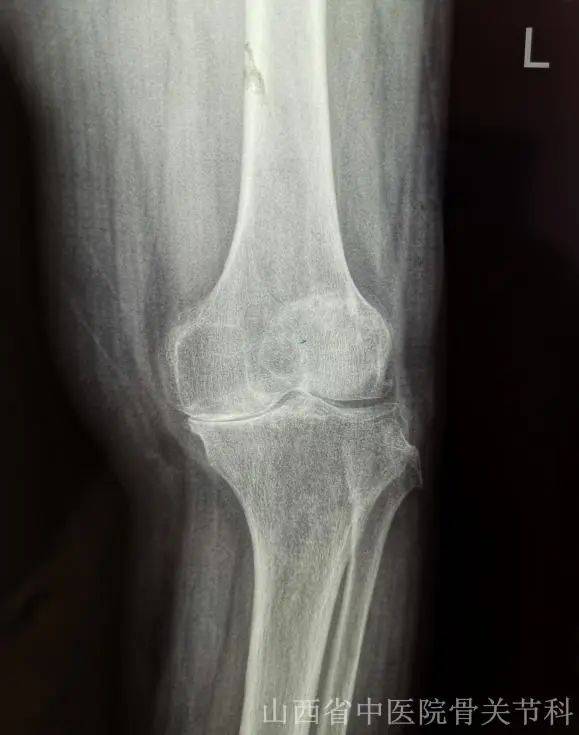

骨关节炎通常累及全身关节,以膝关节最为常见,病理表现为关节软骨的渐进性破坏、软骨下骨硬化和骨赘形成等,临床症状表现为疼痛、关节僵硬、关节活动度显著降低,甚至诱发残疾,其具体的发病机制目前尚未完全明确,是老年人致残的首要原因。

3.关节肿胀和畸形

双手常出现指间关节骨性膨大和畸形,还有膝关节肿胀、内外翻畸形等。